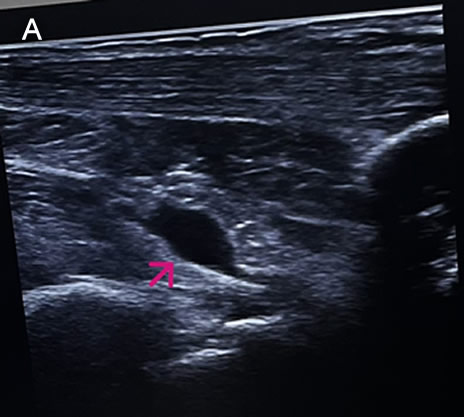

![]() History: A 73-year-old female patient with a past medical history of arterial hypertension presented with a 2-month history of polyarthralgias and subjective fever. Two months before admission, while in Santa Cruz, Bolivia, the patient began experiencing a subjective fever accompanied by chills. One day following symptom onset, she developed severe joint pain involving both wrists, shoulders, and ankles. Two days later, she reported decreased appetite, nausea, vomiting (4–5 episodes per day), and watery diarrhea (6–7 episodes per day). On day 3 of illness, the patient developed localized swelling over the dorsum of the right foot. She received symptomatic treatment with minimal pain relief. One month before admission, the patient experienced severe upper limb pain, which impaired her ability to raise her arms or hold objects, along with intense ankle pain that significantly limited walking. She was evaluated at the rheumatology service and subsequently referred to our outpatient clinic. Epidemiology: The patient was born and currently resides in Lima. She currently has no occupation. She traveled to Santa Cruz, Bolivia, from March to June of the present year to visit her son. There, she reports visiting many tourist attractions, including areas of the highlands and the jungle, where she sustained numerous mosquito bites. Physical Examination on admission: BP: 130/80, RR: 18, HR 87, SpO2: 97% on room air. Musculoskeletal examination revealed tenderness on palpation of the metacarpophalangeal joints, decreased grip strength, and pain with passive and active movement of both shoulders. Additionally, tenderness was noted on palpation of the popliteal region, both knees, and both ankles. The patient presented with difficulty walking due to persistent pain. The rest of the exam was non-contributory. Laboratory: Hemoglobin 12.9g/dL, Hematocrit 36.2%, Platelets 222000, WBC 4500, /µL; with bands 1%, neutrophils 49%, eosinophils 5%, basophils 0%, monocytes 0%, lymphocytes 45% Glucose 88 mg/dl, Urea 42 mg/dl, total proteins 7.15 g/l, albumin 4.07 g/l. The urine exam was normal. An Ultrasound examination demonstrates bilateral synovitis involving the wrist joints and popliteal regions, characterized by joint effusion and synovial thickening. Additionally, there is evidence of bilateral tenosynovitis of the Achilles tendons, characterized by hypoechoic peritendinous fluid and thickening of the synovial sheath. Evaluation of the hindfoot reveals retrocalcaneal bursitis, manifested by distention of the retrocalcaneal bursae with anechoic fluid (IMAGE A, see arrow). UPCH Case Editors: Carlos Seas, Course Director / Paola Nakazaki, Associate Coordinator |